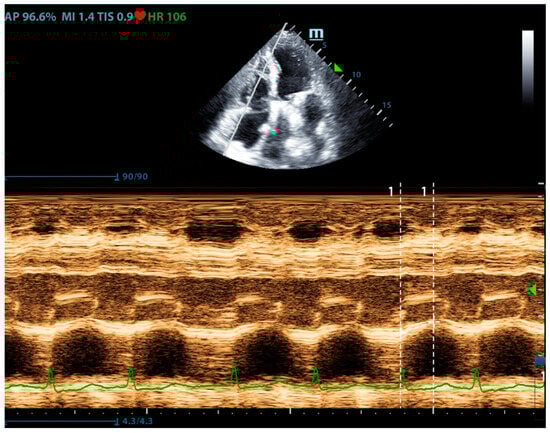

Right ventricular systolic function is an important part of pulmonary circulation assessment. Compared with the left ventricle, which mainly performs a concentric and twisting motion, the contraction of the right ventricle is mainly a long-axis contraction. Therefore, the assessment of right ventricular long-axis systolic function can reflect the overall right ventricular systolic function. Tricuspid annular plane systolic excursion (TAPSE) is the most used indicator to reflect the long-axis contraction of the right ventricle (Figure 4). A TAPSE less than 16 mm indicates right ventricular systolic dysfunction [20]. Although it reflects the longitudinal systolic function, it is well correlated with other indicators that reflect right ventricular systolic function (such as RVEF and RVFAC) [21,22]. Comparing these parameters, TAPSE is most widely used in right heart systolic assessment for its feasibility and reliability. In addition, the systolic peak flow velocity S’ of the right ventricular free wall can also reflect the systolic function of the right ventricle. Tissue Doppler measurement is performed at the base of the right ventricular free wall, and S’ < 10 cm/s indicates right ventricular systolic dysfunction [23,24]. However, this method has poor measurement repeatability for segmental dysfunction and lacks reference values for all age groups, especially the elderly, so it was currently used as a research tool.

Figure 4.

The ultrasound measurement of TAPSE.